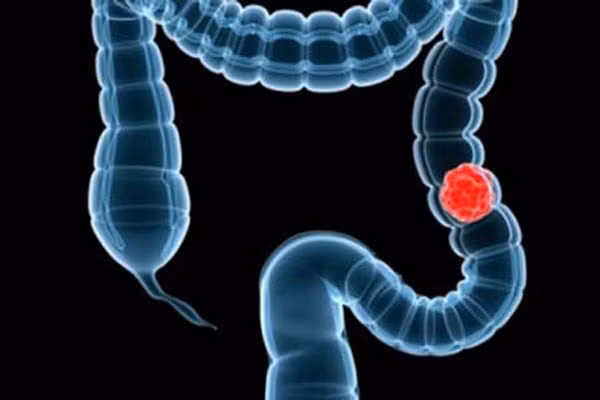

3. Xét nghiệm dấu vết của máu trong phân (FOBT). Như tên gọi của nó, nhằm mục đích phát hiện mất máu tiềm ẩn trong đường tiêu hóa, ở bất cứ nơi nào từ miệng cho đến đại tràng. Xét nghiệm dương tính ("phân dương tính") có thể liên quan đến hoặc xuất huyết đường tiêu hóa trên hoặc xuất huyết đường tiêu hóa dưới và cần phải tiếp tục điều tra thêm nguyên nhân như ung thư đại trực tràng hoặc ung thư dạ dày.

Ung thư ruột già thường bị bỏ qua và do đó được chẩn đoán ở giai đoạn muộn. Đừng tránh làm xét nghiệm này vì sợ hãi. Nó là một phần quan trọng trong phòng chống ung thư và cần được thực hiện tại 50 tuổi trở lên